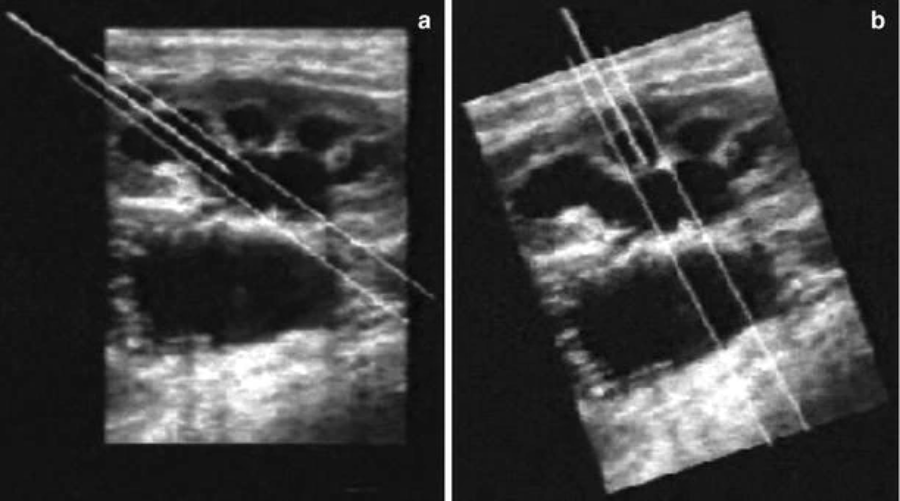

在针刺过程中使用超声或透视进行图像控制取决于设备的可用性、培训和个人喜好。两种方式都已被证明对于初始穿刺目的效果很好。然而,单独使用超声扫描进行全道扩张通常是不可能的,这种方式需要与透视结合使用。许多超声换能器现在都可以使用设计用于容纳针的管腔,并且有人建议通过超声引导的通路提高针放置的准确性可能会降低与 PCNL 相关的并发症的风险。25超声引导的通路为泌尿科医师提供了几个优势:周围结构的实时可视化、前后肾盏的轻松识别以及无辐射(图41.4a 和 b)。在一项透视与超声引导入路的随机试验中,Basiri 证明了这两种方式都是有效的,并指出超声波的使用降低了整个手术的辐射暴露。26

超声引导下经皮肾通路。( a ) 从穿刺的花萼到肾盂有一条直接路径,以便在最佳穿刺中进行后续的管道扩张。( b ) 在次优穿刺中,从穿刺的花萼到肾盂没有直接路径可见